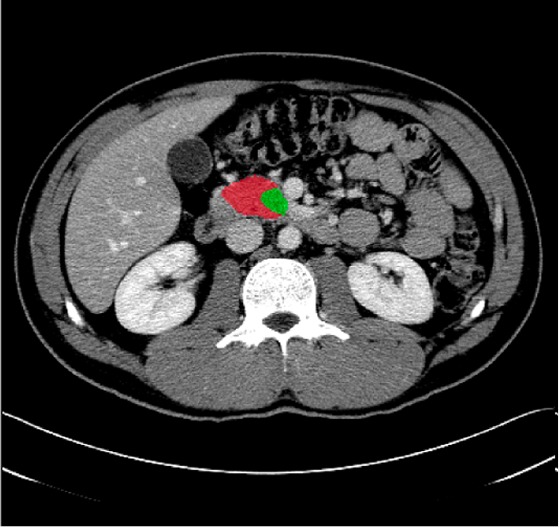

| Annotation & segmentation |

Performs precise annotation and segmentation of medical imaging data using advanced tools and expert teams. |

- AI tools incorporation in ovarian cancer detection: An open-source pipeline that enables deployment of AI-based medical image annotation tools, such as tumor detection and segmentation, into clinical trial workflows, enhancing standardization and reproducibility in imaging analysis.

- Comprehensive AI Annotation Services: Leverage both 2D and 3D annotation across imaging modalities.

- 3D Medical Image Segmentation.